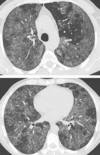

LAM

→ kystes à contours réguliers

Histiocytose X

→ kystes à contours irréguliers

Lymphangioleiomyomatose

Histiocytose

→ noter le respect des

cul de sac costo-diaphragmatiques

Histiocytose X